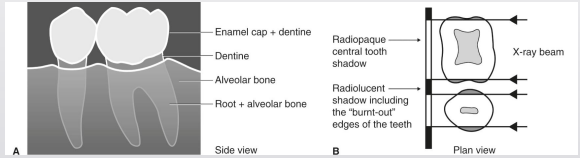

what is the caries process and how it will eventually appear in a radiograph

demineralization → destruction → dec in density → greater x-ray penetration in carious area → radiolucency

what is the susceptible zone

in proximal caries, is between the contact point of the teeth and gingival margins

what is the shape of incipient proximal caries

triangle w broad base at outer surface

why are incipient caries the shape that they are

demineralization occurs along long axes of enamel rods- oriented 90 degrees to enamel surface

what are primary caries

involves DEJ or extends through

what happens to the shape of primary caries once it reaches the DEJ

triangular shape gets lost, lesion gets bigger due to curvilinear or “s-shaped” arrangement of dentin tubules